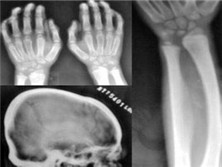

CM1神经节苷脂贮积症

(全身性神经节苷脂贮积症)

CM1神经节苷脂贮积症应该做哪些检查

CM1神经节苷脂贮积症应该做哪些检查?